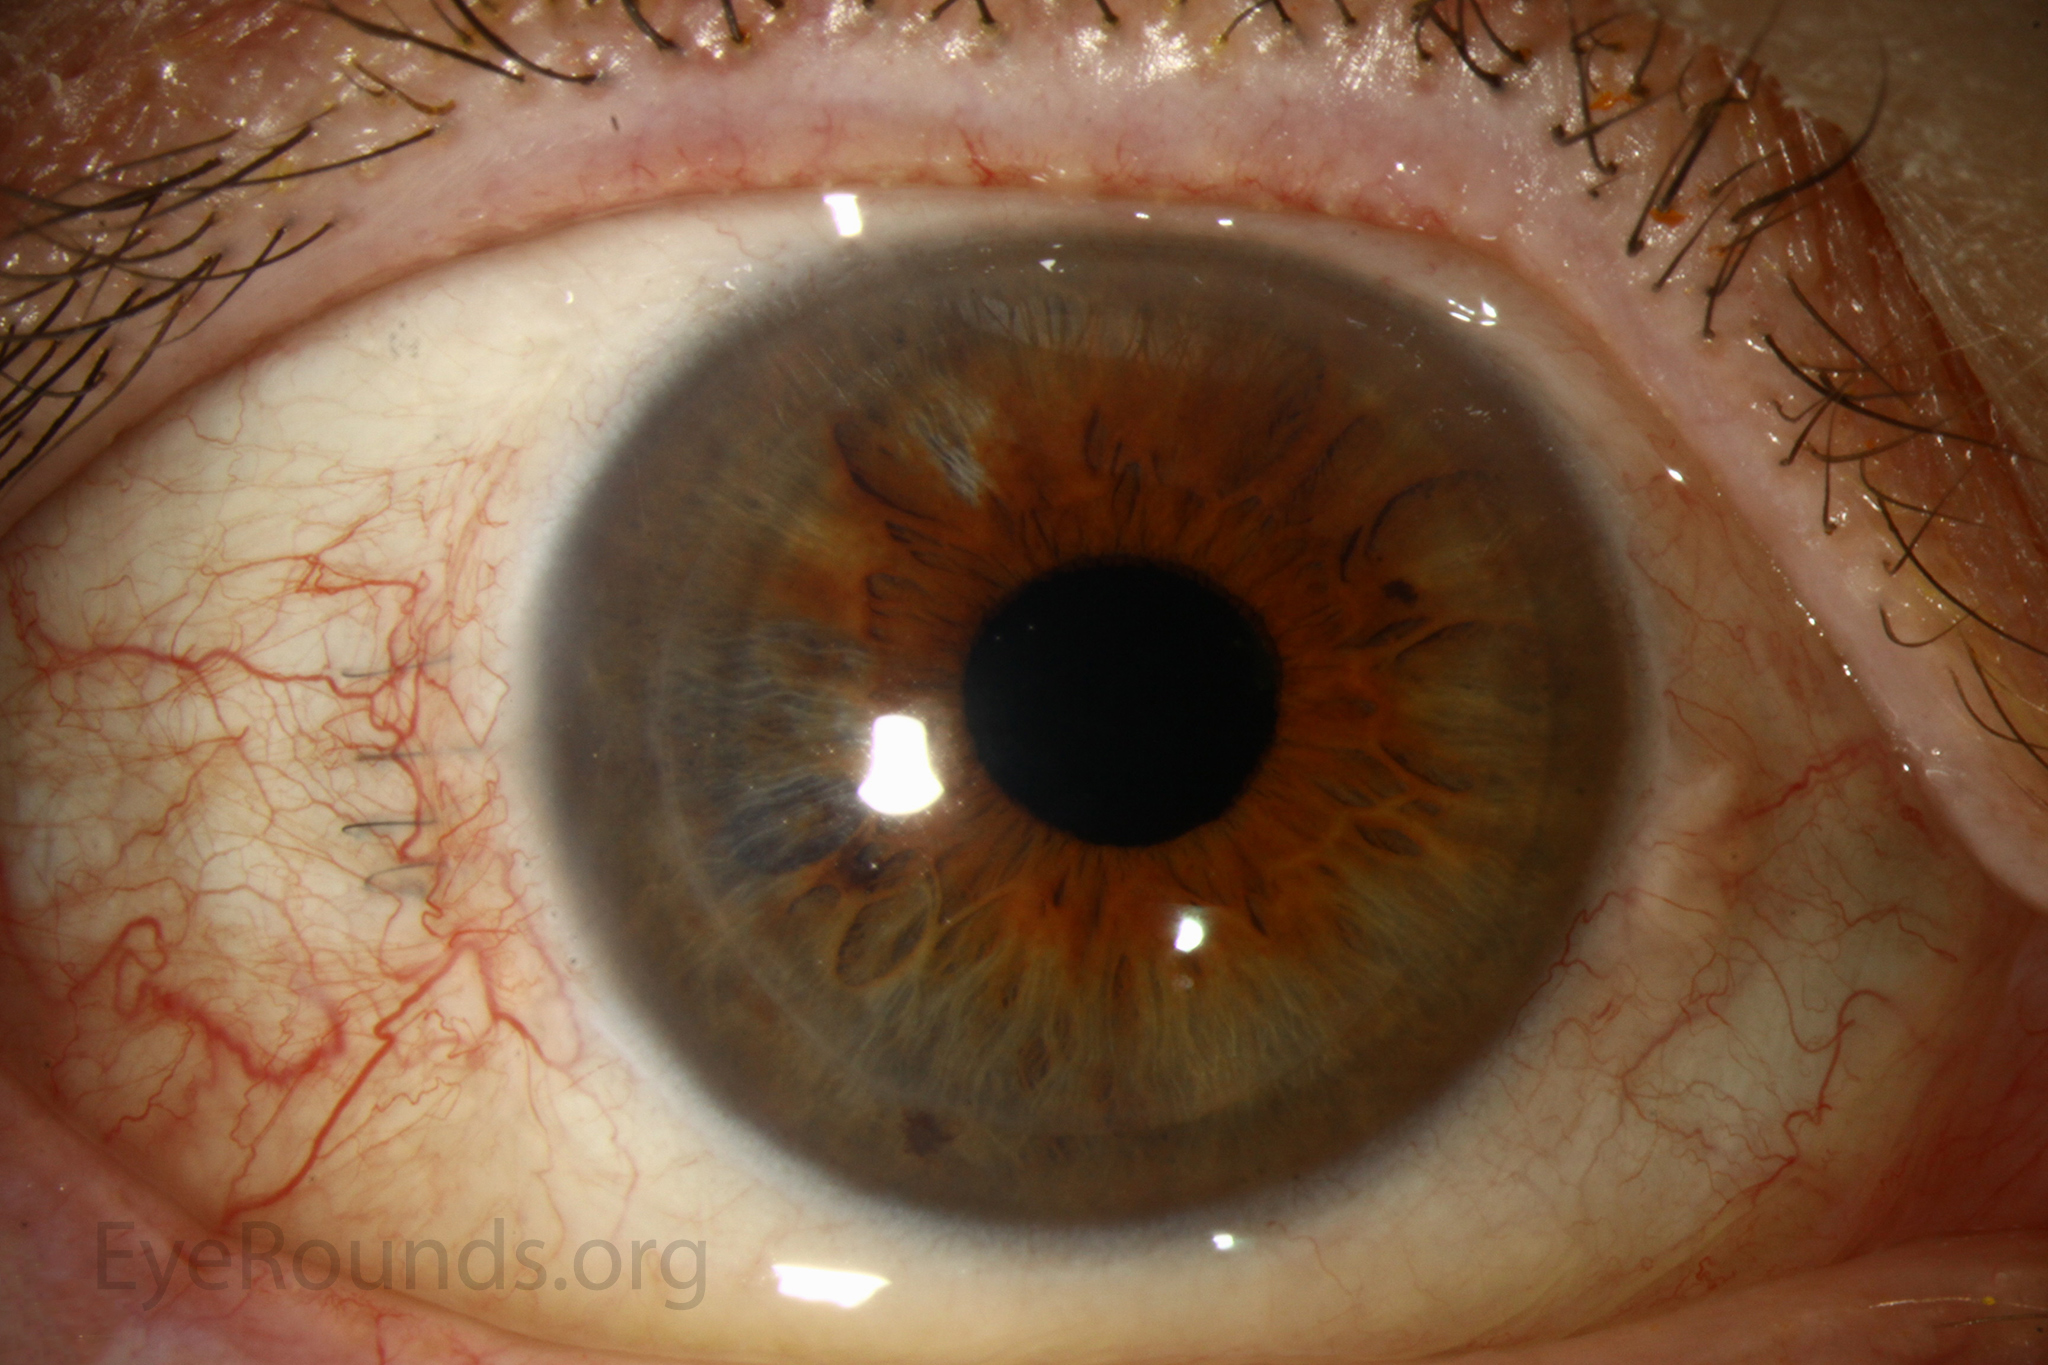

PK is a full-thickness transplant procedure, in which a trephine of an appropriate diameter is used to make a full-thickness resection of the patient's cornea, followed by placement of a full-thickness donor corneal graft. Interrupted and/or running sutures are placed in radial fashion at equal tension to minimize post-operative astigmatism (Figure 2). Later, the sutures are removed selectively to reduce the amount of astigmatism present. A transplant can last decades with proper care (Figure 3). While once the most prominent type of corneal transplant, PK has been supplanted by partial thickness techniques for endothelial dysfunction without significant stromal scarring. PKs are performed primarily for visually significant stromal scarring, opacities with an uncertain status of the endothelium or significant posterior corneal involvement, corneal ectasia (such as keratoconus and pellucid marginal degeneration, especially if there is history of hydrops), combined stromal and epithelial disease (such as Peters anomaly), and infectious or non-infectious corneal ulcerations or perforations (1, 14). A variant of the procedure, the mini-PK, can be used to treat more focal defects in the cornea (Figure 4).

However, postoperative recovery time is relatively long, sometimes taking years to achieve best-corrected visual acuity. Frequently, there is substantial postoperative refractive error due to high regular or irregular astigmatism of the graft, and a higher chance of requiring rigid gas permeable contact lens wear to correct astigmatic error. There is a higher risk of allograft rejection compared with other keratoplasty types. Additionally, PKs carry a higher lifetime risk of wound dehiscence due to the compromised tectonic strength that comes from a full-thickness wound.